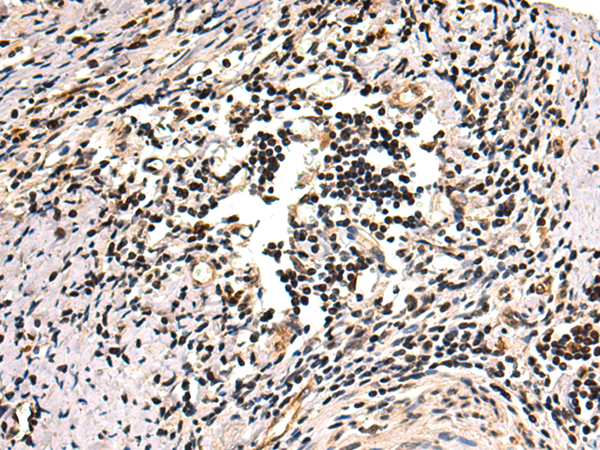

IHC positive control: |

Human prostate cancer and Human esophagus cancer |

IHC Recommend dilution: |

50-100 |